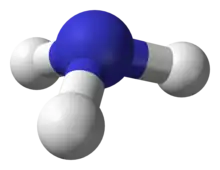

Hepatic encephalopathy can occur in those with acute or chronic liver disease.[4] Episodes can be triggered by infections, GI bleeding, constipation, electrolyte problems, or certain medications.[5] The underlying mechanism is believed to involve the buildup of ammonia in the blood, a substance that is normally removed by the liver.[2] The diagnosis is typically based on symptoms after ruling out other potential causes.[2][6] It may be supported by blood ammonia levels, an electroencephalogram, or a CT scan of the brain.[4][6]

There are various explanations why liver dysfunction or portosystemic shunting might lead to encephalopathy. In healthy subjects, nitrogen-containing compounds from the intestine, generated by gut bacteria from food, are transported by the portal vein to the liver, where 80–90% are metabolised through the urea cycle and/or excreted immediately. This process is impaired in all subtypes of hepatic encephalopathy, either because the hepatocytes (liver cells) are incapable of metabolising the waste products or because portal venous blood bypasses the liver through collateral circulation or a medically constructed shunt. Nitrogenous waste products accumulate in the systemic circulation (hence the older term "portosystemic encephalopathy"). The most important waste product is ammonia (NH3). This small molecule crosses the blood–brain barrier and is absorbed and metabolised by the astrocytes, a population of cells in the brain that constitutes 30% of the cerebral cortex. Astrocytes use ammonia when synthesising glutamine from glutamate. The increased levels of glutamine lead to an increase in osmotic pressure in the astrocytes, which become swollen. There is increased activity of the inhibitory γ-aminobutyric acid (GABA) system and the energy supply to other brain cells is decreased. This can be thought of as an example of brain edema of the "cytotoxic" type.[13]

Despite numerous studies demonstrating the central role of ammonia, ammonia levels do not always correlate with the severity of the encephalopathy; it is suspected that this means that more ammonia has already been absorbed into the brain in those with severe symptoms whose serum levels are relatively low.[4][8] Other waste products implicated in hepatic encephalopathy include mercaptans (substances containing a thiol group), short-chain fatty acids, and phenol.[8]